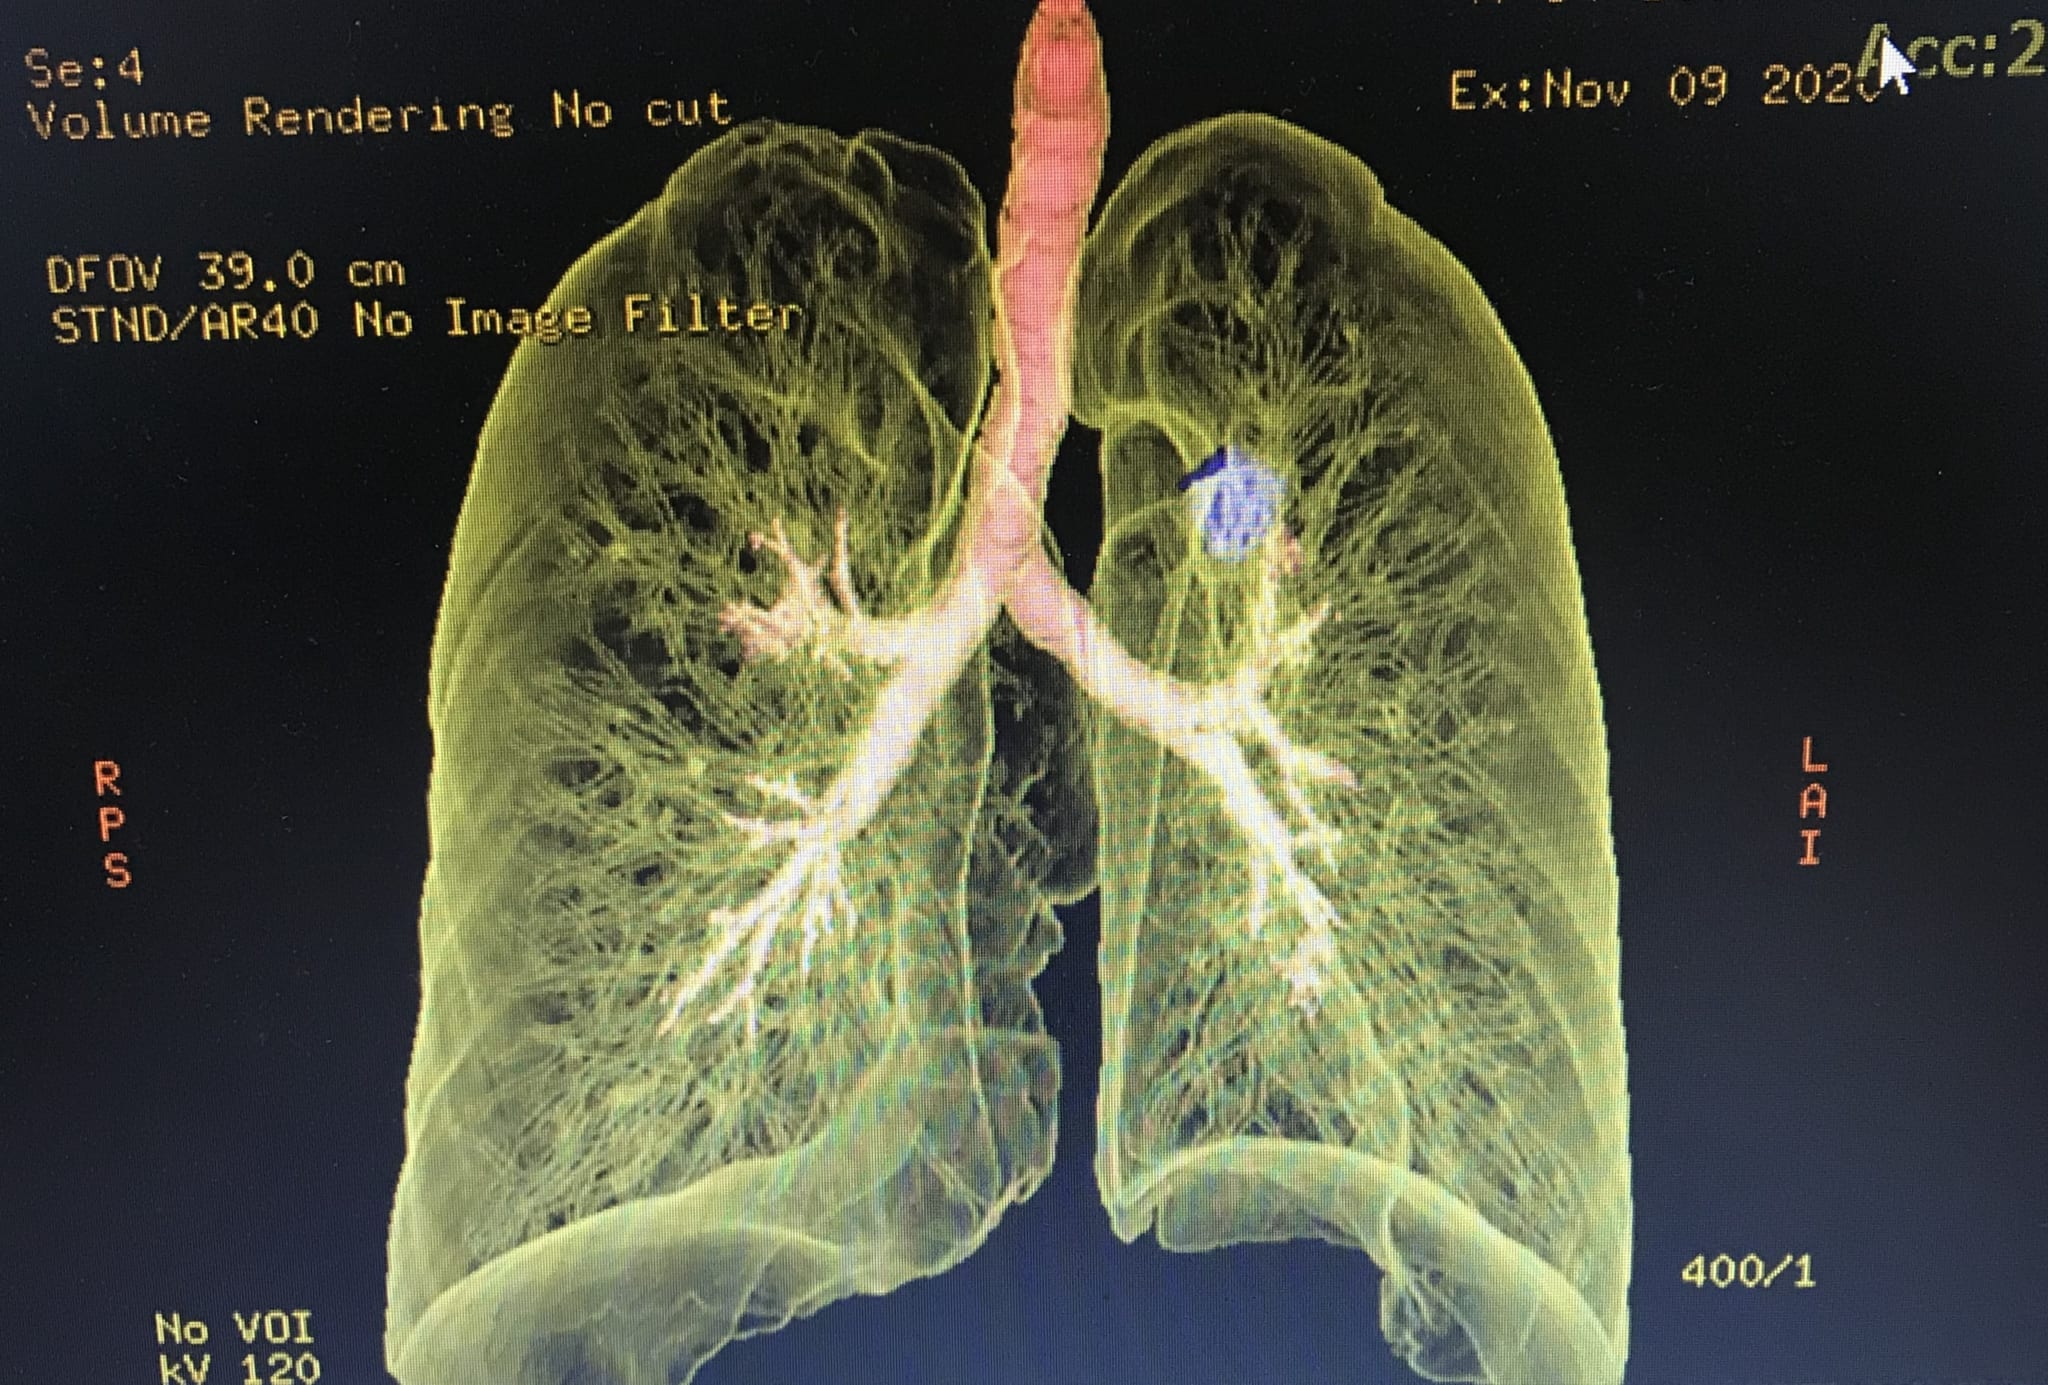

Bệnh nhân được hẹn về nhà theo dõi nhưng khi người bệnh đau tức ngực hai bên, ho đờm vàng nên được gia đình đưa đến khám tại Bệnh viện đa khoa Quốc tế Hải Phòng. Qua thăm khám và chụp CT ngực cho thấy, bệnh nhân có u thùy trên phổi kích thước 2,5×1,7cm.

Với mong muốn xác định khối bất thường ở phổi là lành tính hay ác tính để tìm ra hướng điều trị tốt nhất, chấm dứt tình trạng khó chịu kéo dài cho bệnh nhân. Các bác sĩ Khoa Nội, Bệnh viện đa khoa Quốc tế Hải Phòng đã tiến hành hội chẩn kĩ lưỡng và quyết định thực hiện kỹ thuật sinh thiết phổi. Ths.BSNT Phạm Đắc Thế – Phó Khoa Nội, Bệnh viện đa khoa Quốc tế Hải Phòng đã thực hiện thành công kỹ thuật này. Kết quả mô bệnh học của sinh thiết phổi người bệnh bị ung thư biểu mô tuyến xâm nhập.